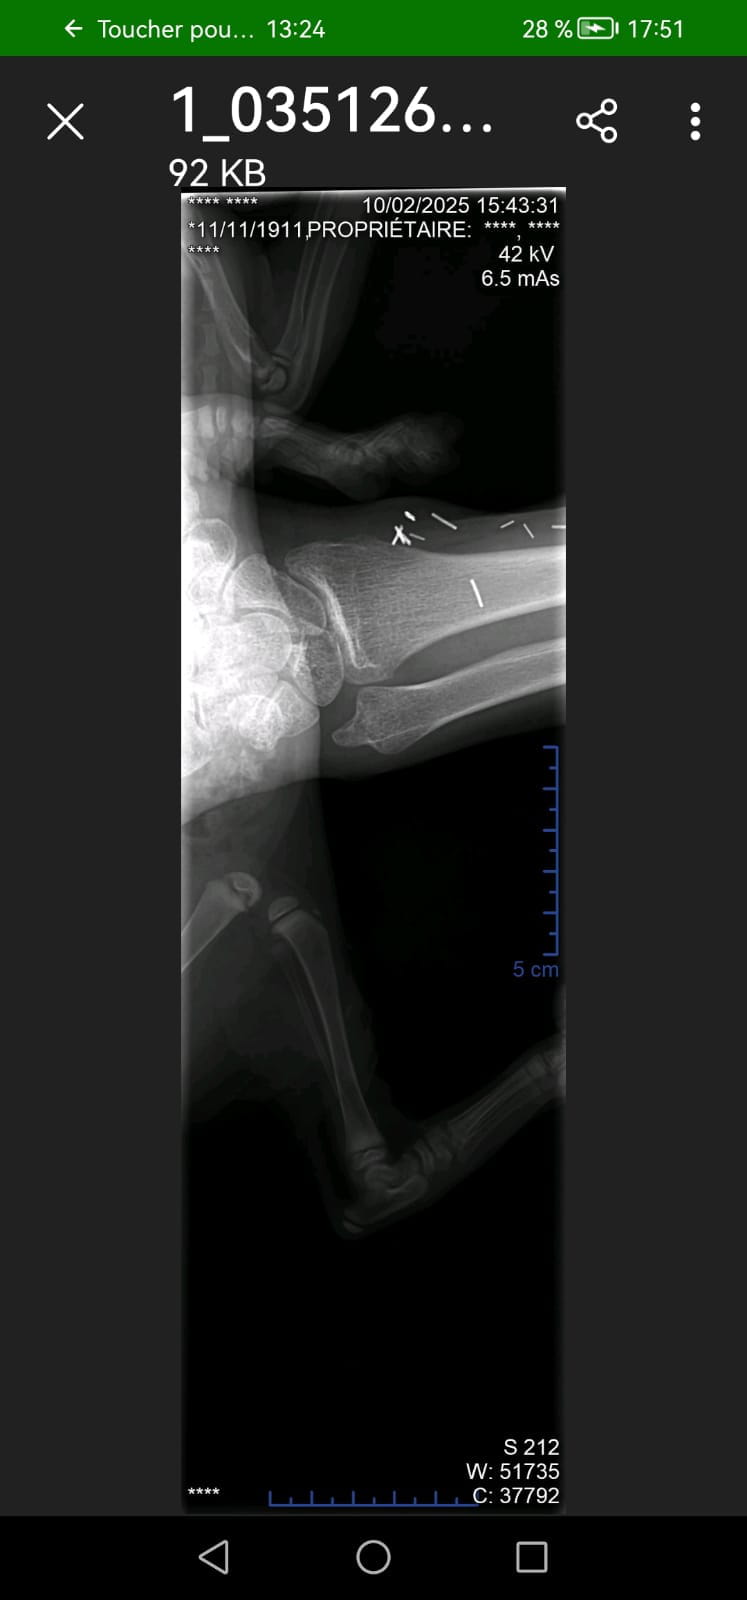

- Os du bras - Guide